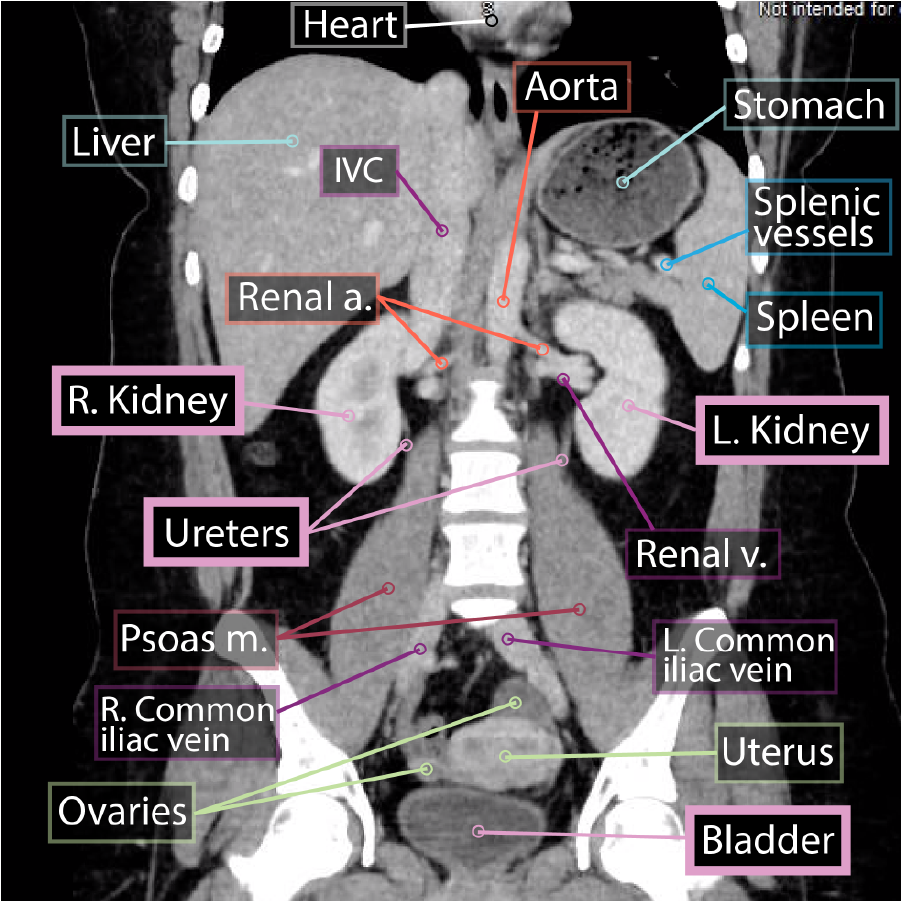

The ureters and urinary bladder are retroperitoneal structures in the abdomen and pelvis (some consider the urinary bladder to be subperitoneal or infraperitoneal).

The kidneys lie on the posterior abdominal wall; these organs filter the blood and produce urine.